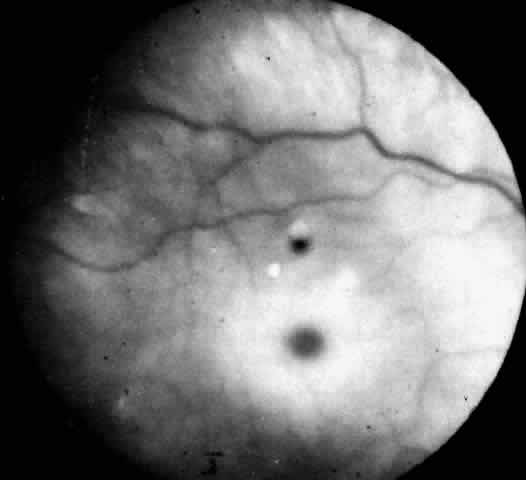

In three patients with type III subacute juvenile neuronopathic Gaucher's disease however, the retina showed a unique retinopathy. The findings in Cogan's case 1 are described: “Both fundi showed discrete white spots randomly distributed in the posterior fundus, especially along the inferior vascular arcades (Fig. 8). The spots varied in diameter from just visible to approximately 0.1 mm and were situated in the superficial retina or on the surface of the retina. Several covered the retinal vessels. The disc and retinal vessels were normal.” The child, an 11-year-old boy, had normal acuity and a full field of vision by confrontation. He had presented at age 3 years with splenomegaly.

Fig. 8. Fundus of a patient with type III subacute juvenile neuronopathic Gaucher"s disease showing discrete white spots in or on the retina along the inferior vascular arcades. At least one spot overlies a vein. The optic disc and retinal vessels were normal. (Cogan DG, Chu FC, Gittinger J, Tyshsen L: Fundal abnormalities of Gaucher"s disease. Arch Ophthalmol 98:2202, 1980. Copyright © 1980, American Medical Association)

Normal vision and similar retinal abnormalities were observed in a mildly mentally retarded 18-year-old woman (case 2) presenting with splenomegaly at age 1 year and in a 6½-year-old boy (case 3) noted to have hepatosplenomegaly in the first year of life. The patients in cases 1 and 3 had conspicuous supranuclear defects of eye movement.